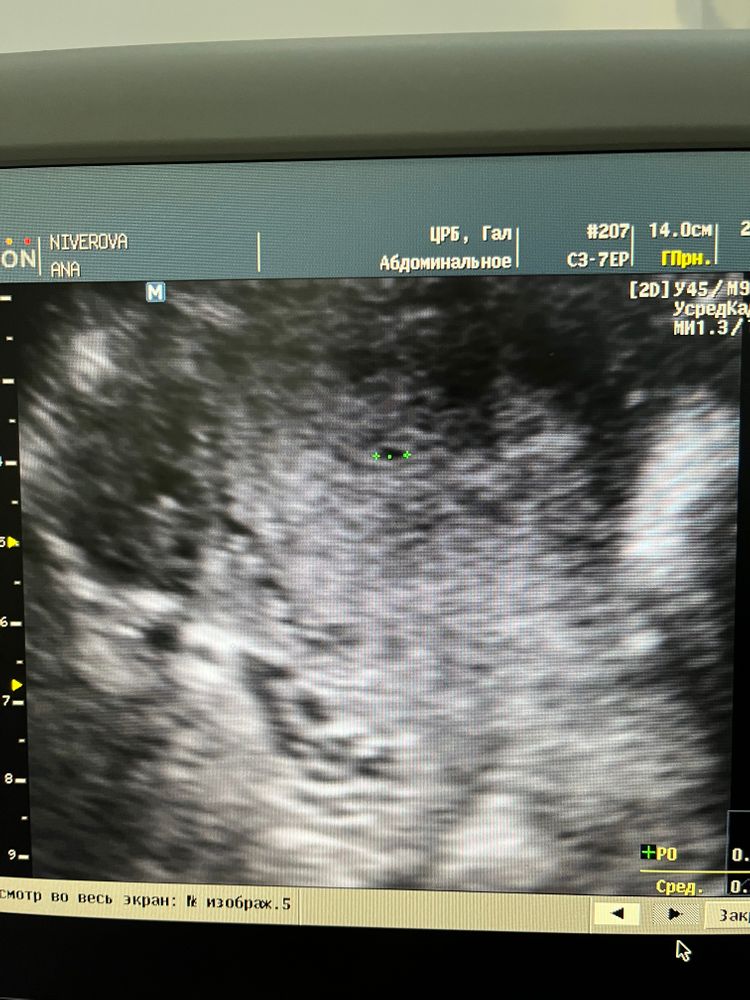

Узи 4 недели

7 недель и УЗИ Оставлю на память!

Это у вас акушерский срок или эмбриональный срок?

Шохида , акушерский. Эмбриональный 1-2